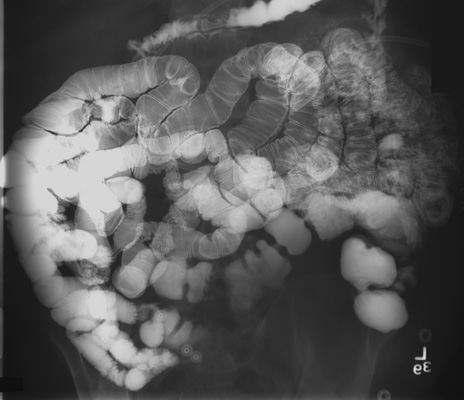

- After the catheter tip has been advanced into the 4th

part of the duodenal loop, return the patient to the supine position. The

final placement of tip of the catheter should be in the region of the

ligament of Treitz, either in the distal duodenal loop or the proximal

jejunum.